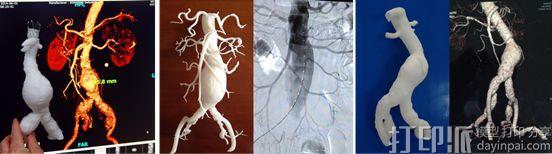

3D打印技术配合chimney技术成功治疗复杂腹主动脉瘤患者

日前,山东大学附属济南市中心医院血管外科治疗一例77岁的复杂腹主动脉瘤患者,此次应用3D打印技术配合chimney技术成功腔内修复近肾动脉腹主动脉瘤为济南首例。

近年来,3D打印技术的迅速发展,能够精准复制动脉瘤,可直视下全方位角度了解病变的解剖学情况。该院血管外科在孟庆义主任领导下,开展了大量的腹主动脉瘤腔内修复手术,都取得了很好的疗效。而此次应用3D打印技术配合chimney技术成功腔内修复近肾动脉腹主动脉瘤更是济南首例。